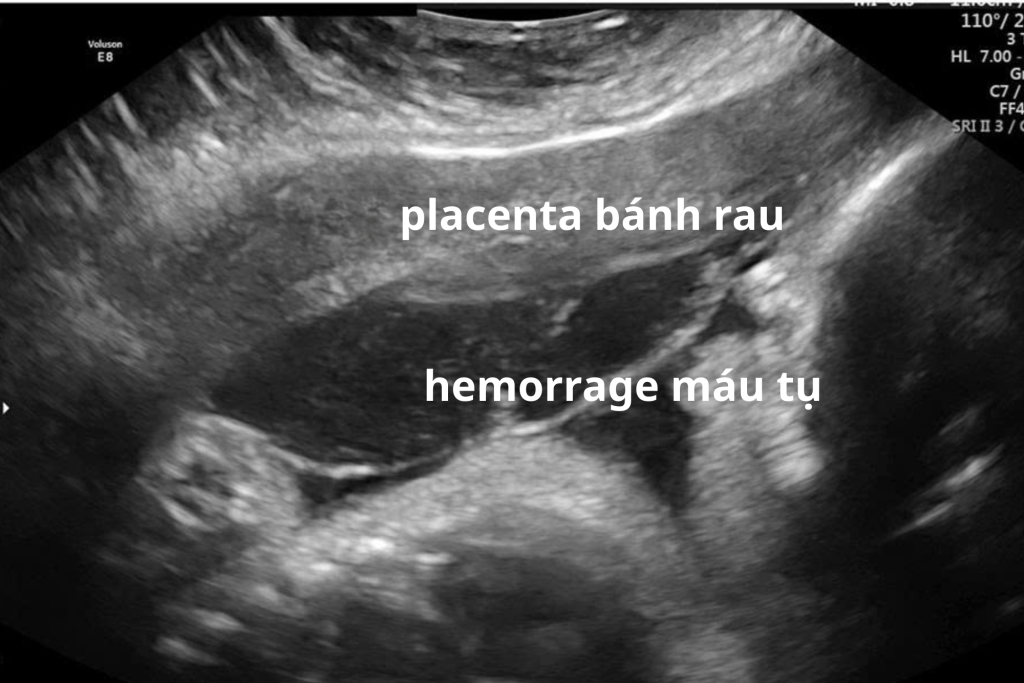

Vai trò của siêu âm trong xử lý nhau bong non

Siêu âm có thể hỗ trợ phát hiện:

• Khối máu tụ sau bánh nhau

• Bánh nhau dày bất thường

Tuy nhiên, siêu âm không loại trừ hoàn toàn nhau bong non nếu hình ảnh chưa rõ. Chẩn đoán chủ yếu dựa vào lâm sàng.